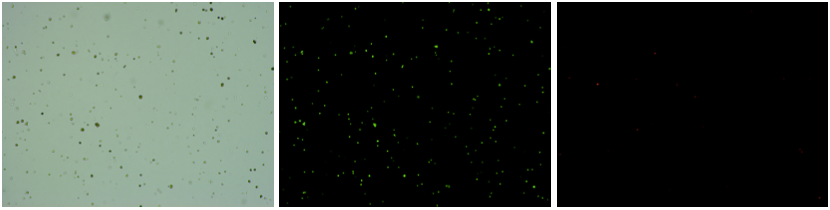

人腎組織樣品,細胞活率:97.86%,結團率:8.68%